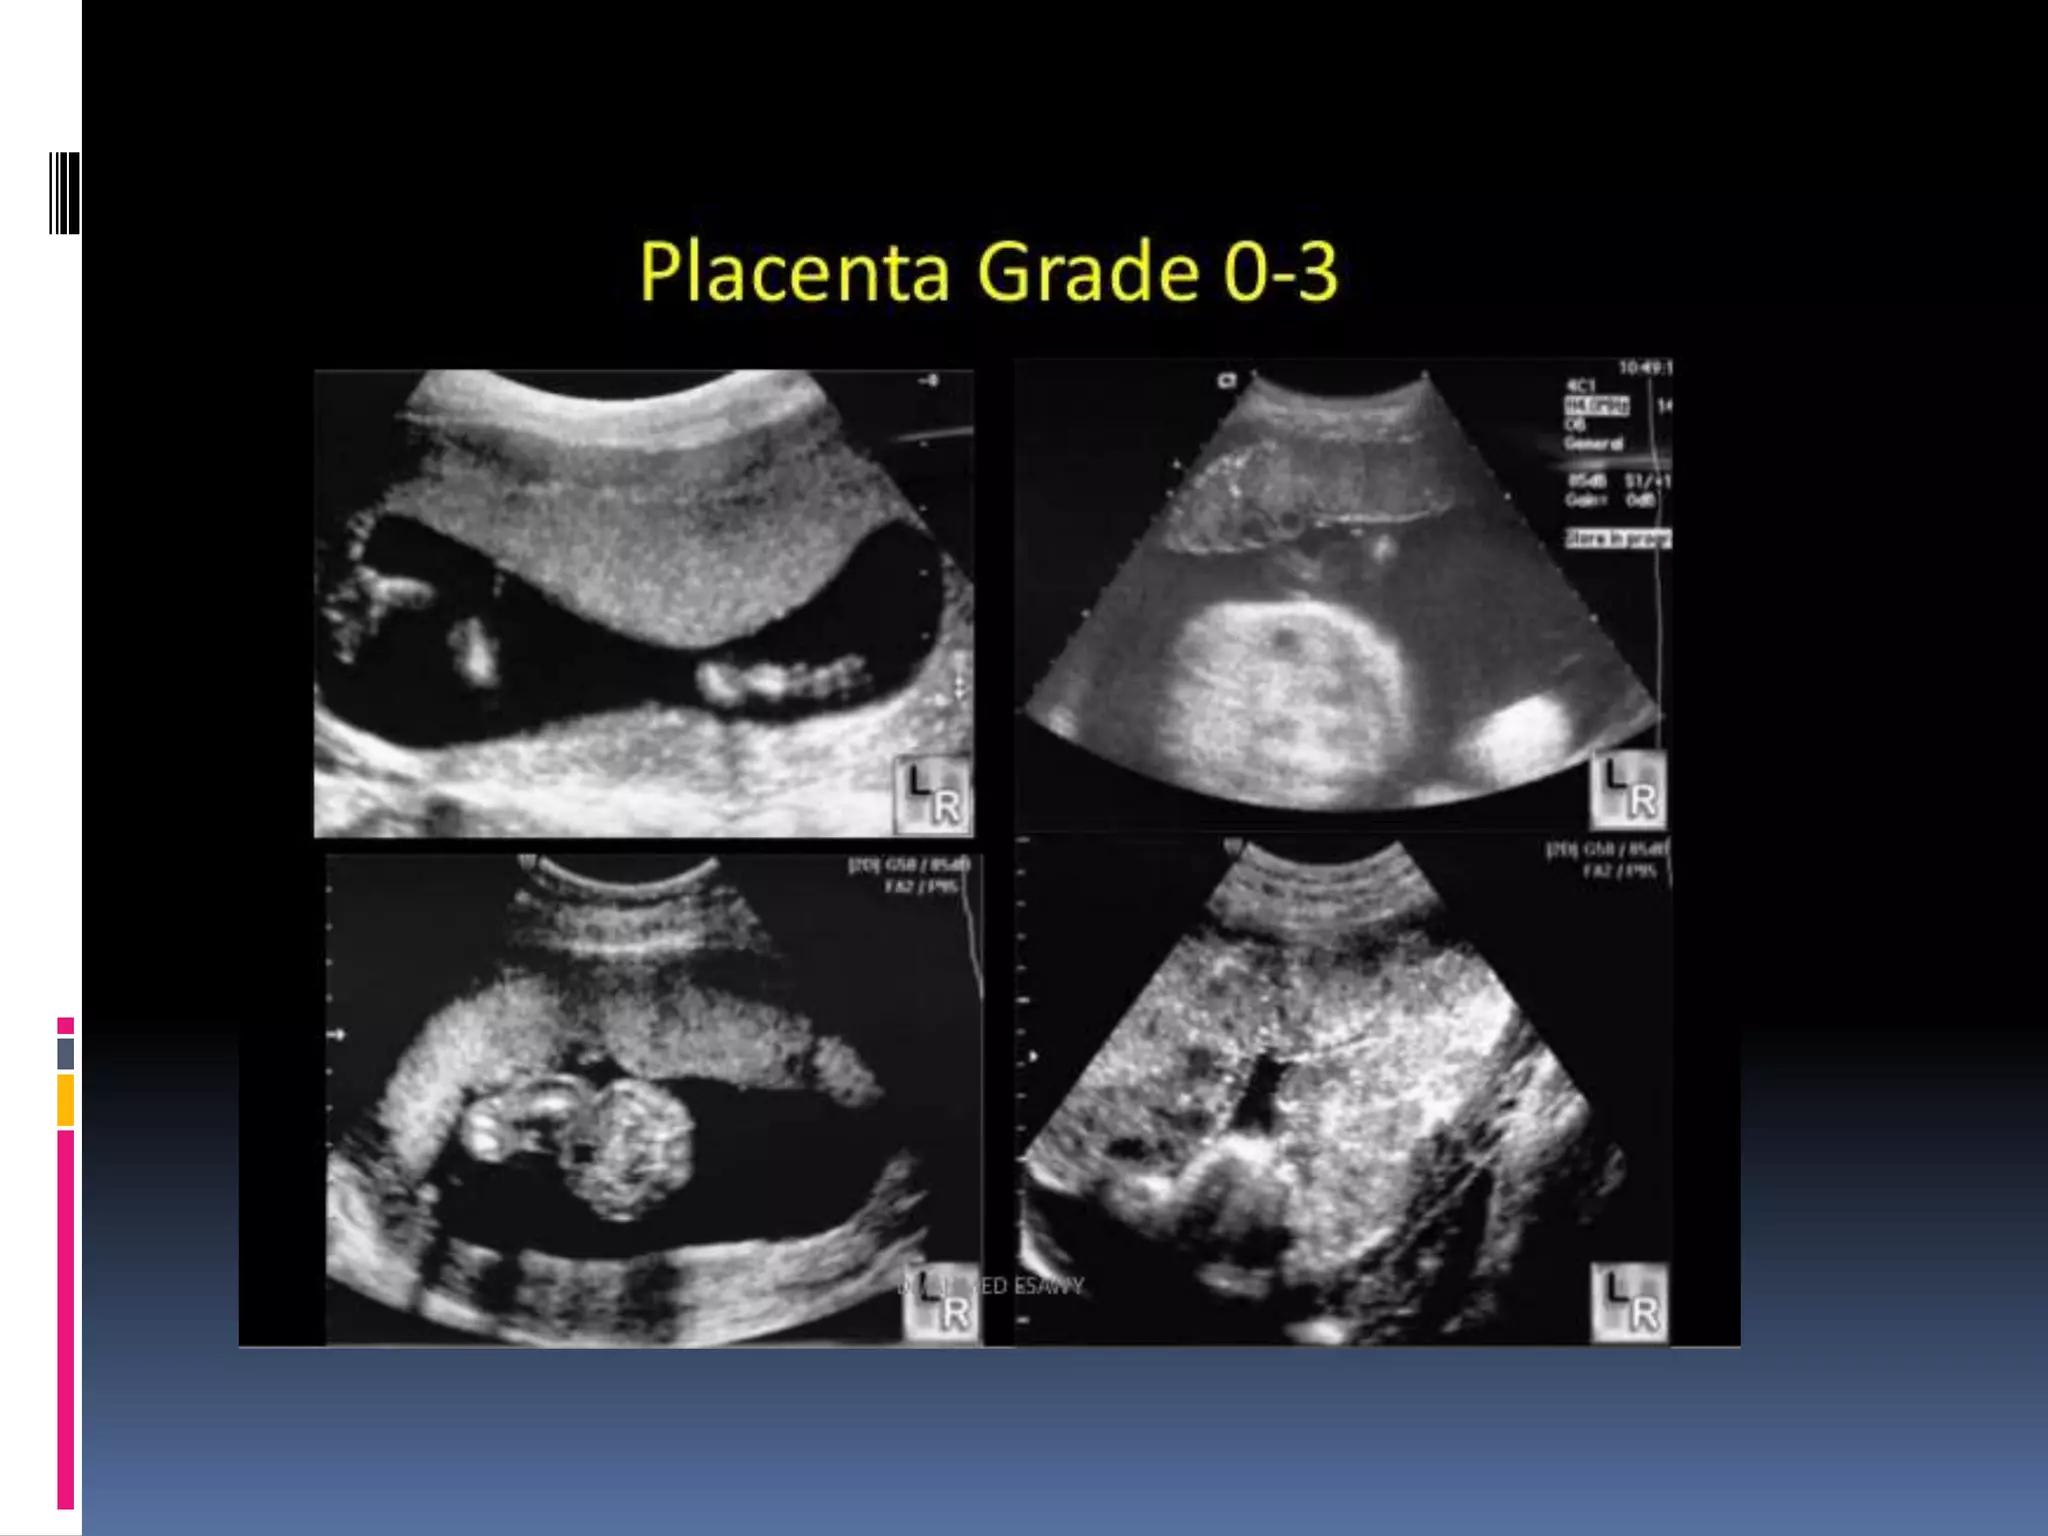

Placental grading

 Grade 0; seen in less than 18 weeks

 Uniform echogenecity with smooth chorionic plate.

 Grade 1 ;18-29 weeks, occasional parenchymal

calcification/ hyper-echoic area.

 Grade II. >30 weeks, occasional basal

calcification/hyper-echoic areas may also have

comma type densities at the chorionic plate.

 Grade III > 39 weeks

 Significant basal calcification.

 Chorionic plate interrupted by indentations.

An early progression to grade III placenta is some

times associated with placental insufficiency.